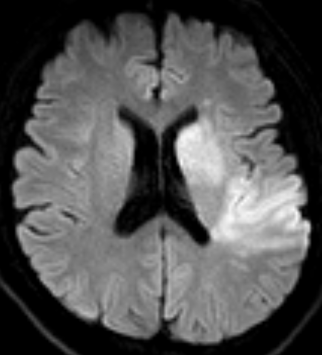

南京市第一医院是国家卫生健康委首批高级卒中中心,设有独立的神经内科急诊及脑血管病绿色诊疗通道。接诊的侯建康主治医师第一时间启动绿通,完善了头部磁共振及血管成像检查,明确了王先生急性缺血性脑梗死的诊断,而梗死原因是王先生脑内两根非常重要的血管(左侧颈动脉和左侧大脑中动脉)发生了堵塞(见图1)。

图1